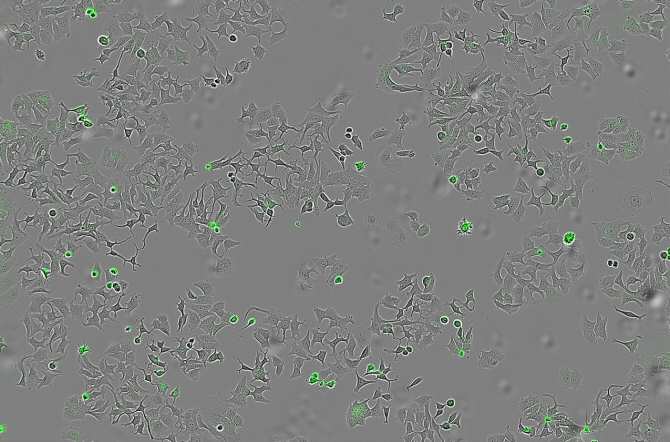

La imagen representa las células de cáncer muertas al activarse su proteína de membrana PAR-1 por la proteasa bacteriana HapA (Imagen: CIC)